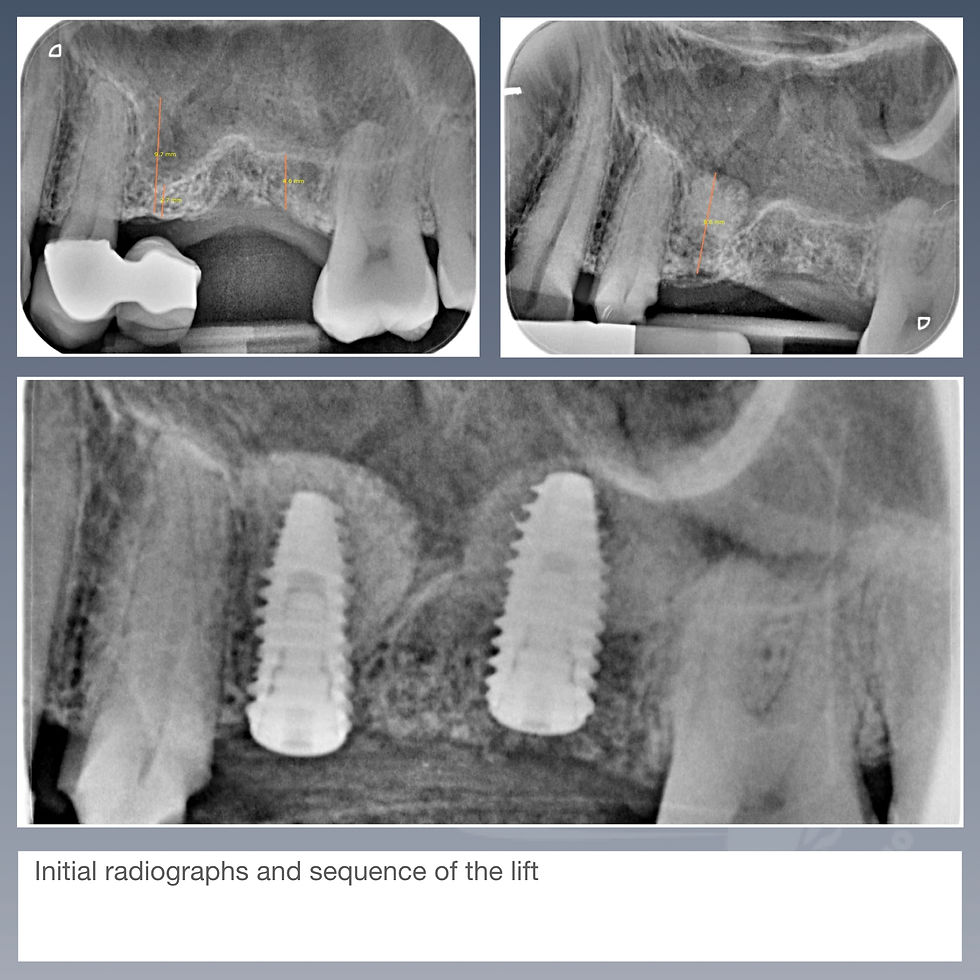

Dr. Fassano, what a fantastic case and long term result. great job. you tried to make thick keratinized tissue. great soft tissue mabagement.